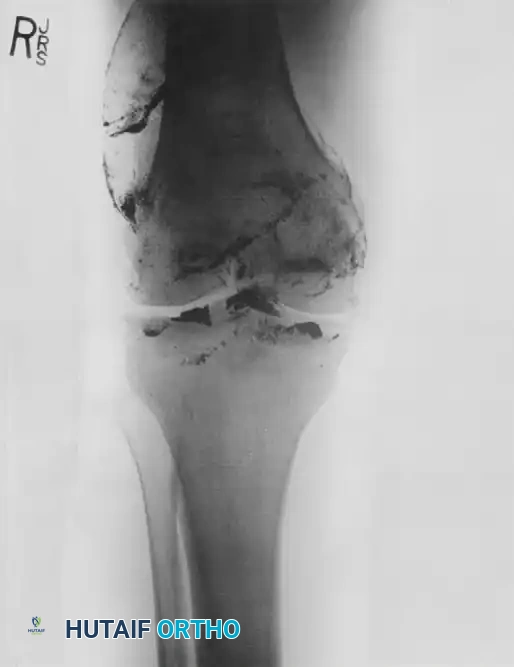

Anteroposterior (AP) and lateral radiographs must be carefully scrutinized for fracture patterns, intraarticular air (pneumarthrosis), bullet fragments, and osteochondral shear injuries. Computed Tomography (CT) is invaluable for preoperative planning, providing 3D spatial information regarding the extent and complexity of the fracture pattern.

Image

FIGURE 1: Anteroposterior view of the right distal femur of an 18-year-old woman with a high-velocity rifle wound. Note the classic “lead snowstorm” pattern and severe comminution indicative of massive kinetic energy transfer. Arteriogram revealed no gross arterial damage.